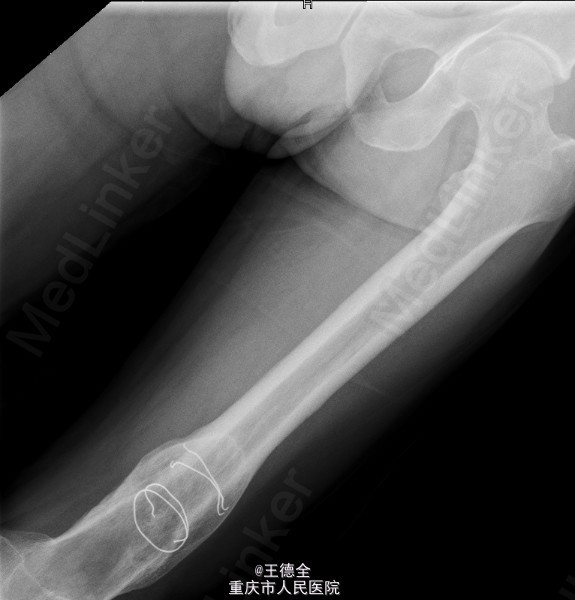

患者男,40岁,因“左股骨下段骨折术后4+年,左膝反复肿痛2年余”入院;自诉于4年前不慎被石块砸伤左大腿,伤后即觉左大腿疼痛,流血,左下肢活动障碍,患者伤后即到当地医院就诊,诊断为:"左股骨下段开放性骨折",予骨折切开复位内固定术,术后3个月下地行走,术后内固定螺钉松动、脱落,近两年来出现左膝关节肿胀、疼痛,活动时肿胀、疼痛症状加重,无畏寒发热、肢端麻木等,患者病后曾到当地医院就诊,予服药治疗后症状无明显好转,为进一步诊治遂来我院就诊,门诊拟"左膝骨性关节炎"收住我科,病程中,患者一般情况尚可,睡眠、饮食可,大小便正常,体重无明显改变。目前积极完善术前检查,拟做关节镜下关节清理术+左膝腘窝囊肿切除手术治疗。